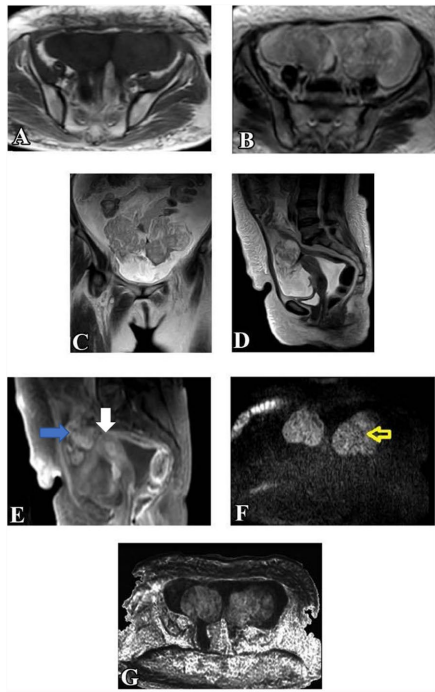

来自曼苏拉大学医学院(Dina EL-Metwally等)的研究团队在《Egyptian Journal of Radiology and Nuclear Medicine》发表的重要研究,对此给出了肯定答案。研究人员创新性地采用1.5T MRI设备,通过标准化扫描方案(包含T2WI、DWIb=1000、ADC值测量及增强T1WI等序列),对50例患者56个附件肿块进行前瞻性评估。研究首次系统验证了O-RADS MRI评分在non-DCE-MRI中的诊断效能,为临床提供了一种更高效的决策工具。

关键技术方法包括:1)多参数MRI扫描(T1/T2加权、DWI、ADC映射);2)双盲阅片(由3年与14年经验的放射科医师独立评估);3)O-RADS MRI标准化评分(基于肿块形态学、增强特征及扩散特性);4)病理学对照(54例手术标本+2例两年随访)。

MRI特征分析

研究揭示恶性肿块的典型标志:93.3%存在强化实性成分(vs 良性7.6%),96.7%表现扩散受限(ADC值0.942±0.24 vs 良性1.79±0.15),70%伴腹膜种植。这些发现为影像鉴别提供了客观依据。

O-RADS分类表现

肿块风险分层显示:80.8%良性归为O-RADS 2(如单纯性囊腺瘤),73.3%恶性归为O-RADS 5(如高级别浆液性癌)。值得注意的是,当将O-RADS 3(如黏液性囊腺瘤)视为恶性时,系统灵敏度达100%且阴性预测值(NPV)完美,这对排除恶性肿瘤具有重要临床价值。